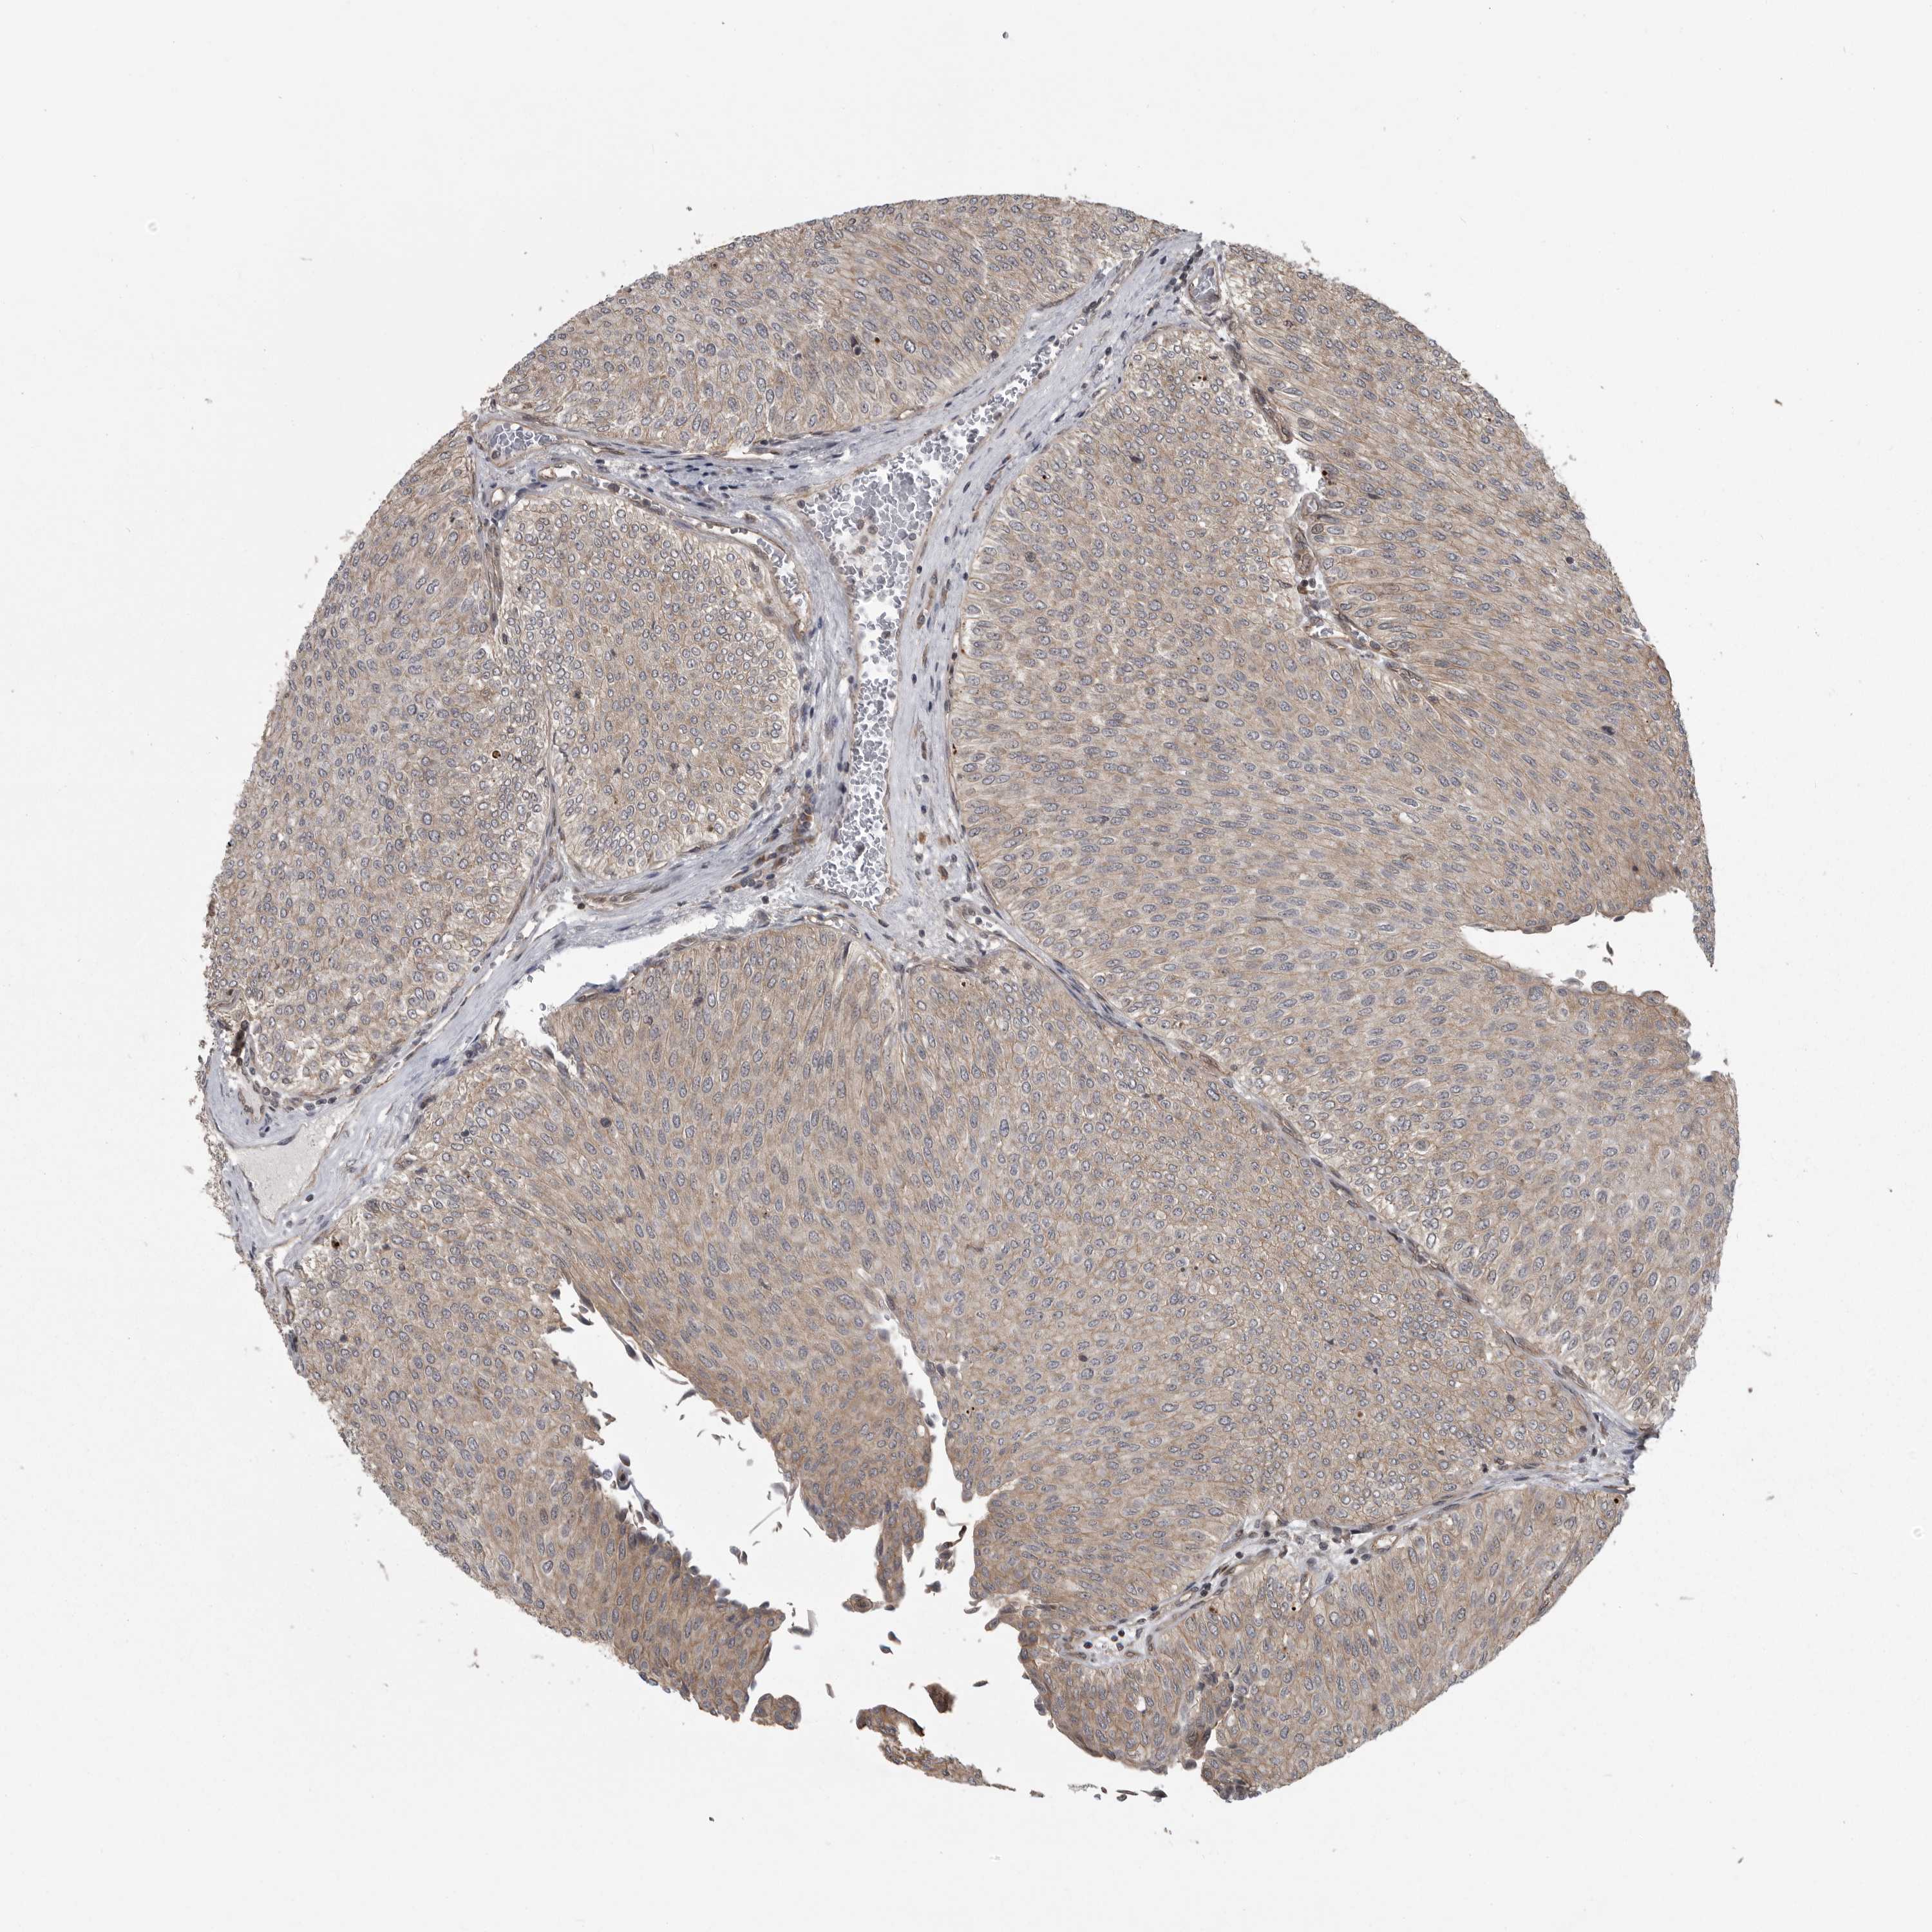

UROTHELIAL CANCER - Protein expressioni

A mouse-over function shows sample information and annotation data. Click on an image to view it in a full screen mode. Samples can be filtered based on level of antibody staining by selecting one or several of the following categories: high, medium, low and not detected. The assay and annotation is described here.

Note that samples used for immunohistochemistry by the Human Protein Atlas do not correspond to samples in the TCGA dataset.

Antibody stainingi

Antibody staining in the annotated cell types in the current human tissue is reported as not detected, low, medium, or high, based on conventional immunohistochemistry profiling in selected tissues. This score is based on the combination of the staining intensity and fraction of stained cells.

Each image is clickable and will lead to virtual microscopy that enables deeper exploration of all samples and also displays staining intensity scores, fraction scores and subcellular localization as well as patient and tissue information for each sample.

Antibody HPA026283

Staining

High

Medium

Low

Not detected

Intensity

Strong

Moderate

Weak

Negative

Quantity

>75%

75%-25%

<25%

None

Location

Nuclear

Cytoplasmic/membranous

Cytoplasmic/membranous,nuclear

Urothelial carcinoma, Low grade

Urothelial carcinoma, High grade